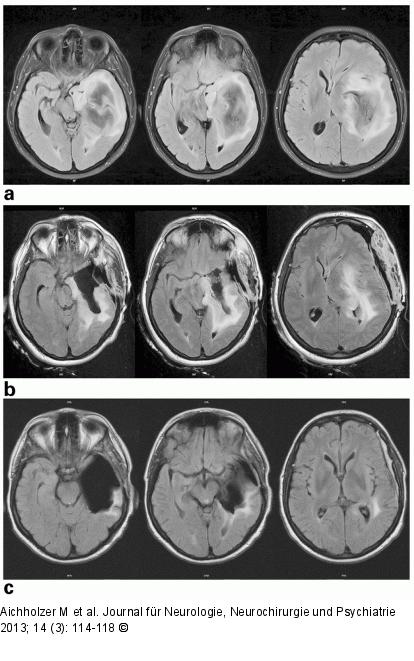

Abbildung 1a-c: iMRT 46-jährige Patientin mit Wortfindungsstörungen, Gedächtnisstörungen, psychomotorischer Verlangsamung und Gesichtsfeldausfall; (a) präoperativ 02/2012 (axial Flair); (b) intraoperativ 02/2012 (axial Flair): Resttumoranteile in den dorsalen Tumorausläufern und temporomesial dem Hirnstamm anliegend; (c) postoperativ 06/2012 (axial Flair): Geringe Tumorreste temporodorsal an das Trigonum angrenzend; Histologie: anaplastisches Astrozytom WHO III. |

46-jährige Patientin mit Wortfindungsstörungen, Gedächtnisstörungen, psychomotorischer Verlangsamung und Gesichtsfeldausfall; (a) präoperativ 02/2012 (axial Flair); (b) intraoperativ 02/2012 (axial Flair): Resttumoranteile in den dorsalen Tumorausläufern und temporomesial dem Hirnstamm anliegend; (c) postoperativ 06/2012 (axial Flair): Geringe Tumorreste temporodorsal an das Trigonum angrenzend; Histologie: anaplastisches Astrozytom WHO III. |